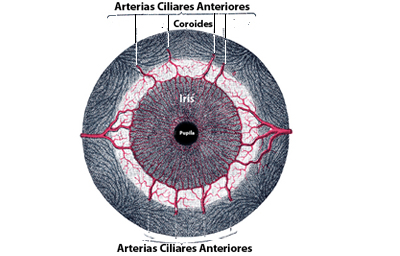

La vascularización proviene de las arterias ciliares largas y las ciliares anteriores, que penetran formando una malla radial en el estroma iridiano.

Existe el círculo vascular mayor del Iris situado en la periferia que ya es estroma del cuerpo ciliar, y el círculo menor en el collarete.

Histologicamente son arteriolas, capilares y vénulas con características especiales: no tienen lamina elástica pero si una túnica adventicia que les da el aspecto de un tubo dentro de un tubo, cuya finalidad podría ser protegerlas de acodamientos y posible obstrucción, en el movimiento de dilatación.

Otra característica importante es que los capilares son continuos, no tienen fenestraciones evitando así que macromoléculas sanguíneas plasmáticas, pudieran pasar al estroma iridiano; la cantidad de proteínas derivadas del plasma que están en el humor acuoso es el 1% respecto al encontrado en el plasma en condiciones de normalidad, un mayor porcentaje causaría dispersión de la luz en la cámara anterior y degradaría la calidad de la visión. En la inervación del estroma iridiano hay fibras nerviosas mielinizadas y otras que no lo están. Tiene fibras simpáticas, parasimpáticas y también sustancia P inmuno-reactíva sensorial, que llegan a través de la división oftalmica del V par.1